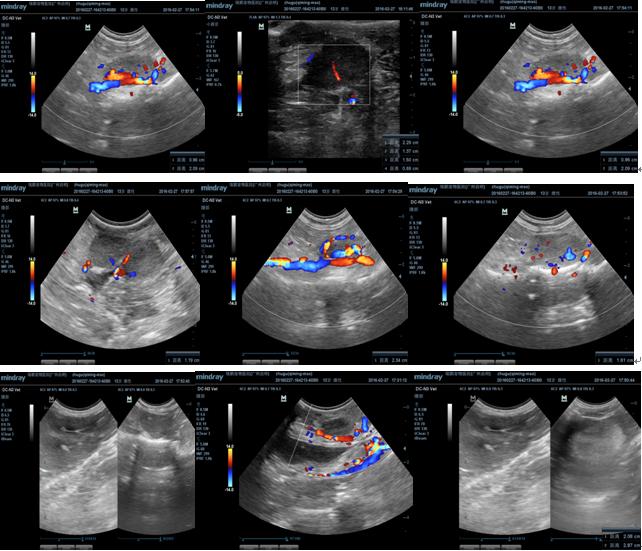

3.2.5 B超检查

超声提示:

1 乳腺肿瘤

2 腹股沟淋巴结炎或腹股沟淋巴结肿瘤

3 肝脏左叶实质结节,疑似肝脏肿瘤。